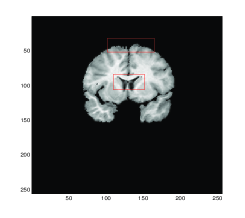

Figure 4 shows the transformed template images for all four methods. We can see that Gaussian curvature gives the best result inside the red boxes in comparison with the diffeomorphic demon, the linear and mean curvature models as depicted in Figure 4 (d).

Refer to caption

(a) Model D

(b) Model LC

(c) Model MC

(d) Gaussian curvature

Figure 4: Test 2: A pair of Brain MR images. Comparison of Gaussian curvature with competing methods. The transformed template image using (a) Model D, (b) Model LC, (c) Model MC, and (d) Gaussian curvature. Notice the differences of these three images inside the red boxes. Considerably more accurate results are obtained, particularly within these significant regions, by employment of the Gaussian curvature model.

The values of the quantitative measurements for Test 2 are recorded in Table 2 where the lowest values of ε𝜀\varepsilon are given by the Gaussian curvature model indicating higher similarity between the transformed template result and the reference image. However, our proposed model required more time than the other models since the model consists more variables than the others.